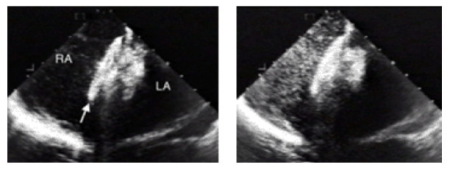

Prof. Haass: Normalerweise wird ein kathetergeführter Schirmverschluss durchgeführt. Dabei wird ein Führungskatheter unter örtlicher Betäubung und Röntgenkontrolle meist von der Leistenvene in das Herz und durch das PFO vorgeschoben. Die Defektgröße wird durch einen Ballonkatheter abgemessen und im Anschluss das passende Schirm-Implantat gewählt. Der Katheter wird mit dem Schirmchen armiert, in den linken Vorhof vorgeschoben und aufgeklappt. Im Anschluss wird der Katheter ein Stückchen zurückgezogen und das Gegenstück im rechten Vorhof freigegeben, sodass der Defekt nun "druckknopfartig" von beiden Seiten verschlossen ist. (siehe Abbildungen unten) Der wesentliche Vorteil besteht in einem gesicherten Septumverschluss und der Vermeidung einer Langzeittherapie mit Antikoagulanzien (Tabletten zur Gerinnungshemmung, Anm. d. Red.).

Dasselbe Herz (siehe Abbildungen oben) nach Verschluss mit einem Schirm-Implantat, welches man deutlich an der Verdickung des Vorhofseptums erkennen kann. Der Pfeil zeigt auf die rechte Seite des Schirmchens.